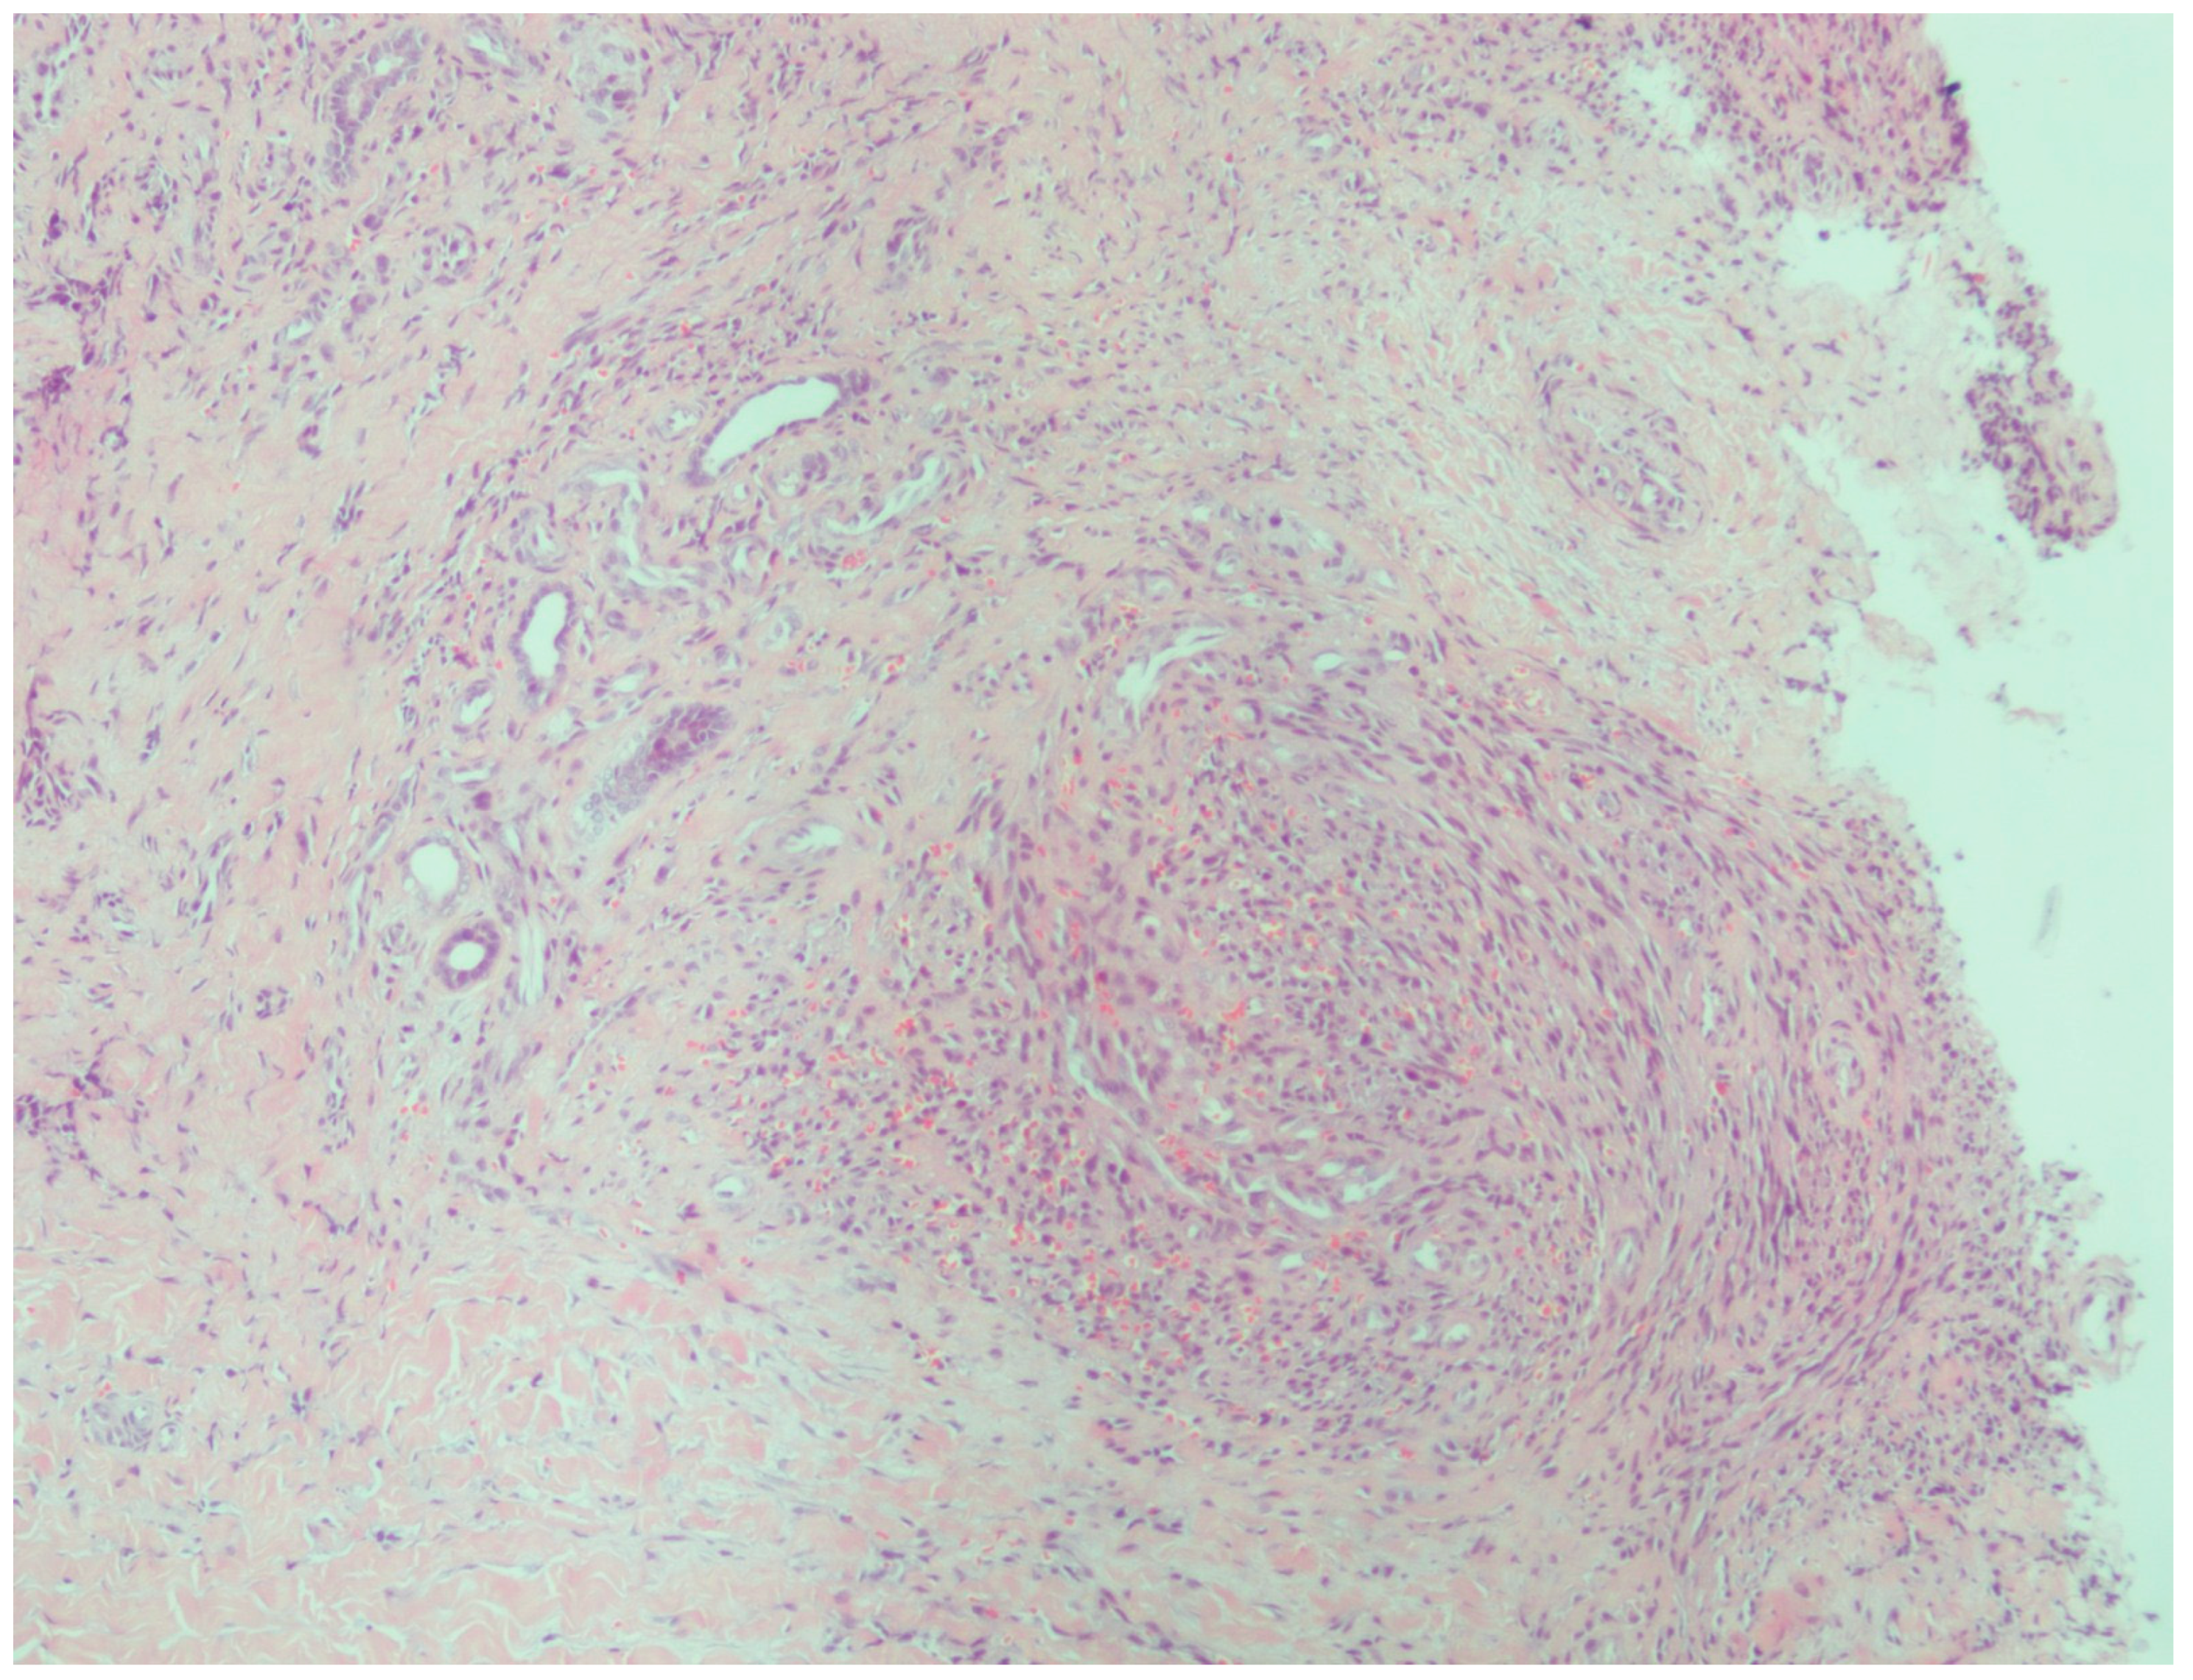

2.5. Histopathological Processing and Immunohistochemistry